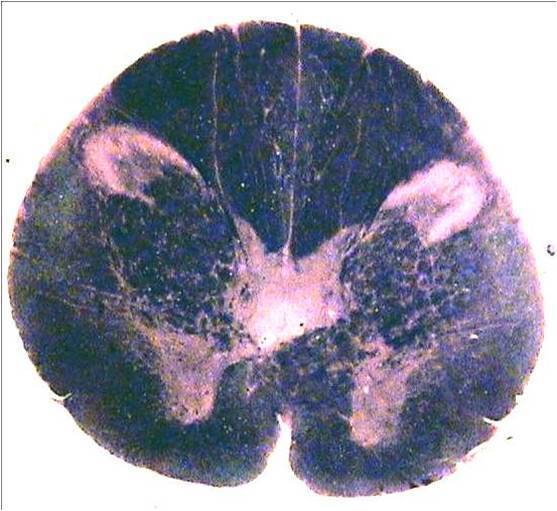

Question

presiona la estructura marcada y escoge la opción que entregue la información correcta de la estructura.

Image:

e623c2f0-0881-4300-8332-8e288c17986d (image/jpeg)

Answer

axones del cordon dorsal

somas del trigemnino espinal

Fasciculo espinotalamico

todas son falsas